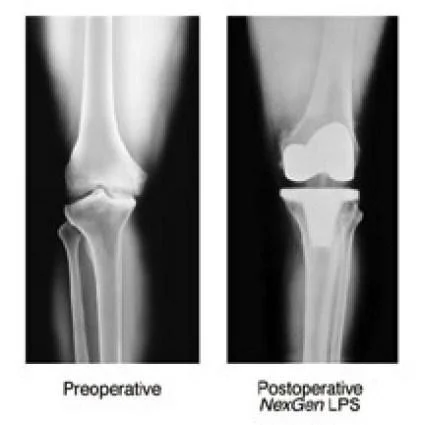

Corrective Osteotomy

- Realign axis & Redistribute weight bearing

- Indication:

- young patients with mild to moderate OA

- Thin & active with mobile joint

- Knee

- Valgus producing proximal tibial osteotomy

Arthroplasty:

- Joint replacement

- Partial

- Total

Total Joint Arthroplasty:

-

Replacing the native joint with prosthesis

Indicated:

- Old patient with deformed, stiff & painful joint.

Contraindication:

- Young active patients

- Infected joint

- Neuropathic joint

Used:

- All joints.